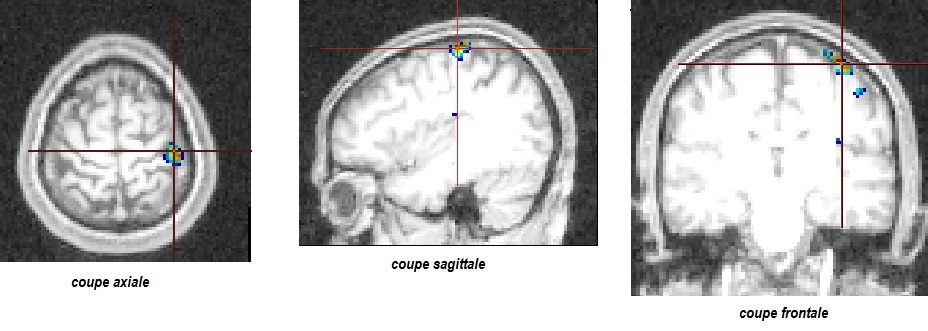

3coupes_mgVSmd_sujet13112

Anne Florimond

Dernière modification

03/11/2015 13:21